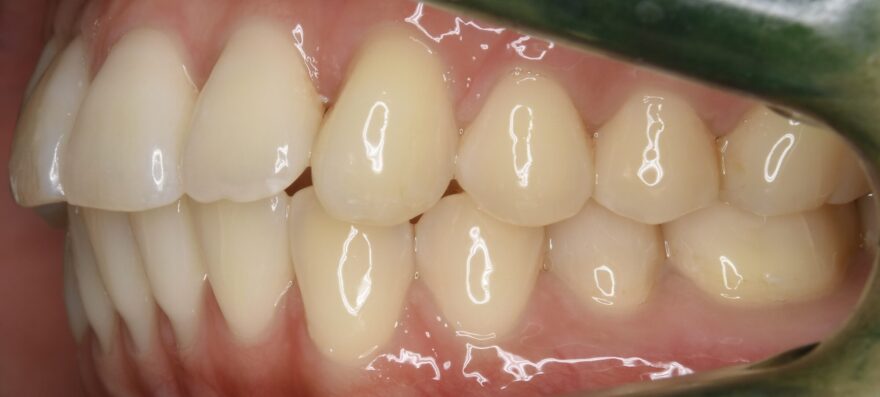

治療後の口腔内写真

約2年半の動的期間(歯を動かす時期)で、ここまで美しい歯並びになりました。

歯科矯正用アンカースクリュー無しだと、治療期間は更に1年長くなってしまったと思います。

前歯の捩れも無くなりました。